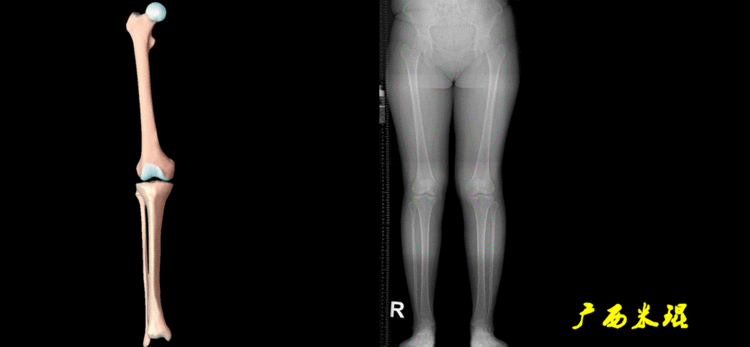

下肢力线及相关角度测量的前提是必须拍摄标准的站立位也就是负重位的下肢全长片。目前这样的照片都是放射科的技师在电脑上拼接出来的,大部分医院的DR都能够做到这一点。

无论如何,拍摄出来的下肢全长片必须包含髋关节中心、膝关节中心及踝关节中心,否则对临床是无用的。有了一张下肢的全长照片,我们需要确定下肢关节的中心点,通过中心点画出下肢的各种轴线,然后利用轴线与关节线的相交得出各种所需要的角度。

2、画出下肢的轴线确定髋关节、膝关节、踝关节的中心点后,我们才能了解下肢的几个轴线。(1)解剖轴股骨和胫骨的骨干中线为解剖轴,股骨解剖轴和胫骨解剖轴的夹角正常值为174°±1°。

(2)机械轴机械轴是连接近端和远端关节中心点的直线。

机械轴要分前后位及侧位,站立前后位(也就是冠状面)股骨头中心与踝关节中心的连线通过膝关节中心,这是下肢的机械轴线,也就是下肢力线,常说Mikulicz线。冠状面的力线评估在临床工作中最常用、最基础、最重要。

开始接触时可能我们对这些轴有点混乱,通过下面的这张图片就能清楚的了解下肢几个轴之间的关系。